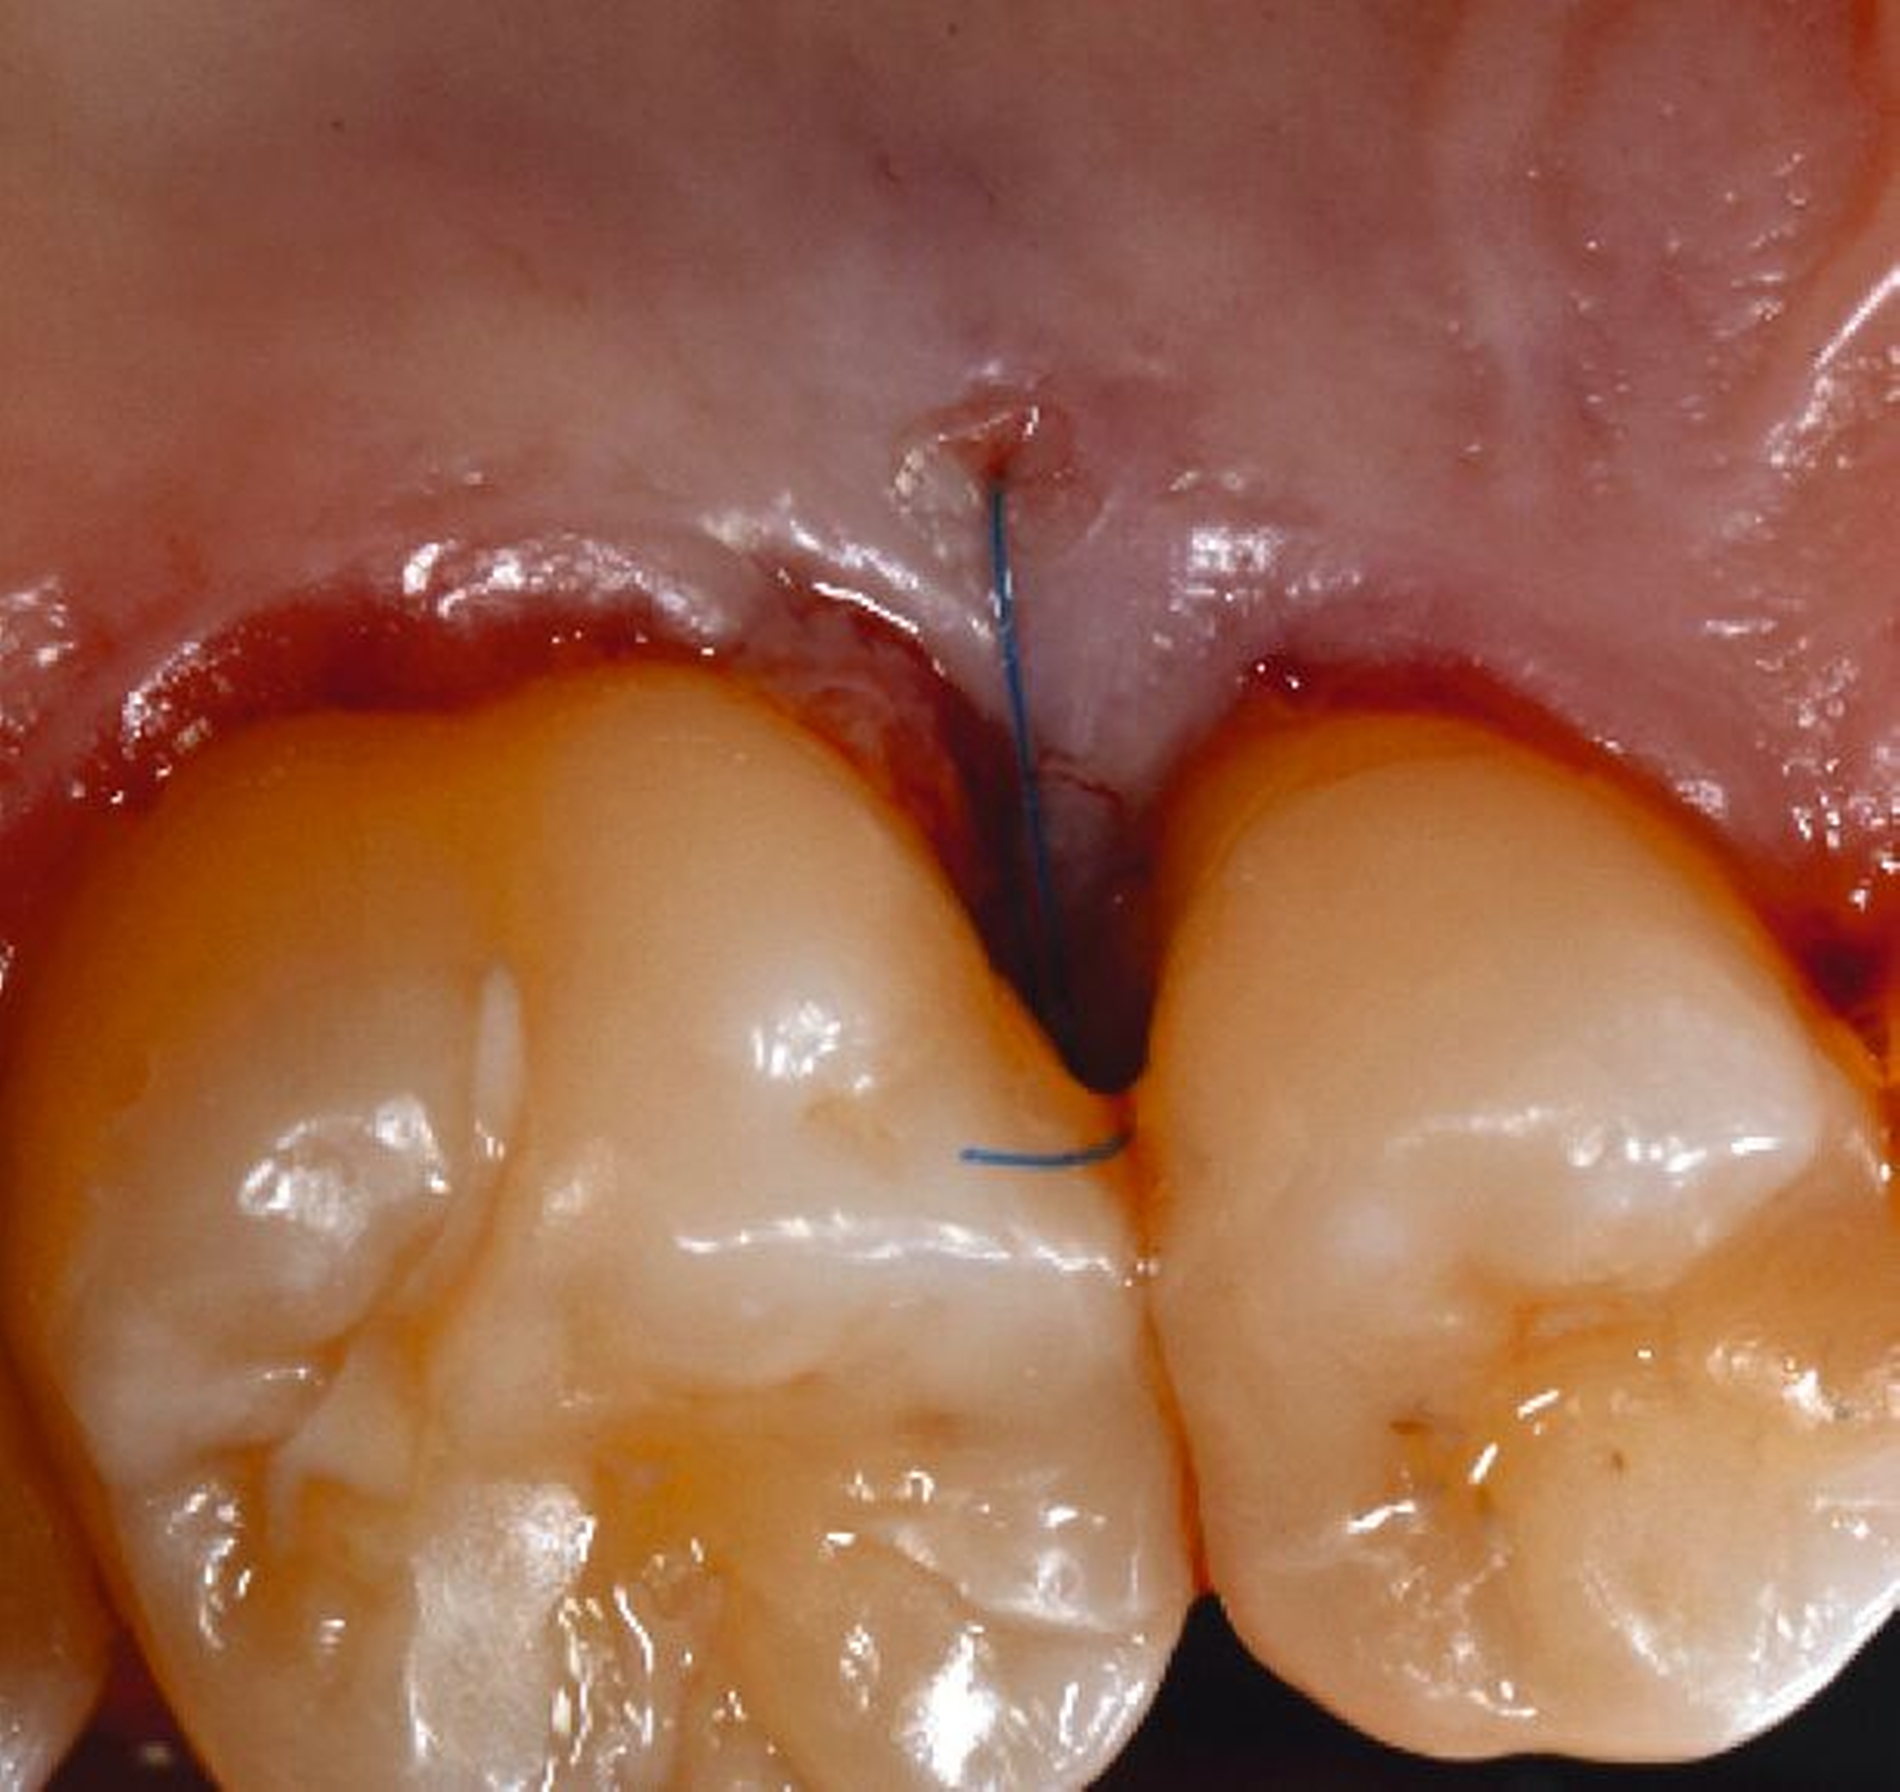

Ziel ist es, einen ausreichenden Zugang zum Defekt für eine sorgfältige Instrumentierung und die Applikation des Biomaterials zu erhalten. Bei isolierten Defekten können vertikale Entlastungsinzisionen verwendet werden. Alternativ kann der Lappen nach lateral zu den benachbarten Zähnen erweitert werden. Keratinisiertes Gewebe sollte durch intrasulkuläre Inzision und die Anhebung eines Mukoperiostlappens erhalten werden. Das Granulationsgewebe wird entfernt und die freiliegenden Wurzeloberflächen werden sorgfältig mit Handinstrumenten, oszillierenden Scalern (optional mit fein diamantierten Spitzen) oder rotierenden Instrumenten gereinigt. Wurzelanomalien wie Schmelzvorsprünge/-perlen sollten entfernt werden. Wenn EMD Teil der Regenerationsstrategie ist, wird es in der Regel nach einer zweiminütigen Wurzelkonditionierung mit Ethylendiamintetraacetat (EDTA) und Spülung mit steriler Kochsalzlösung angewendet. Anschließend kann ein Knochentransplantat/-ersatzmaterial verwendet werden, um den Furkationsdefekt aufzufüllen.

Alternativ kann eine GTR-Barrieremembran mit oder ohne zusätzlichen Defektfüller appliziert werden. Die Barrieremembran wird mit einer resorbierbaren Umschlingungsnaht befestigt, um den Furkationseingang abzudecken und die Wund- und Koagulumstabilisierung zu fördern. Um eine vollständige Abdeckung der Barriere zu ermöglichen, kann das Periost durchtrennt werden, um den Lappen leicht koronal zu verschieben. Der Lappen wird mit einer Umschlingungsnaht und Einzelknopfnähten über den vertikalen Entlastungsinzisionen oder mit interdentalen Nähten im Fall eines lateral extendierten Lappens in einer koronalen Position gesichert. Der Patient wird angewiesen, für einen Zeitraum von bis zu vier Wochen auf die mechanische Plaqueentfernung im Operationsgebiet zu verzichten. Während dieser Zeit werden Chlorhexidin-Spülungen oder -Gel verwendet. Der Patient kehrt zur Kontrolle der Wundheilung nach ein und zwei Wochen zurück, wenn die Nähte entfernt werden. Die Interdentalhygiene und die mechanische Plaqueentfernung werden nach vier Wochen wieder aufgenommen. Zudem wird ein individuelles Recallprogramm zur unterstützenden Parodontitistherapie (UPT) festgelegt.